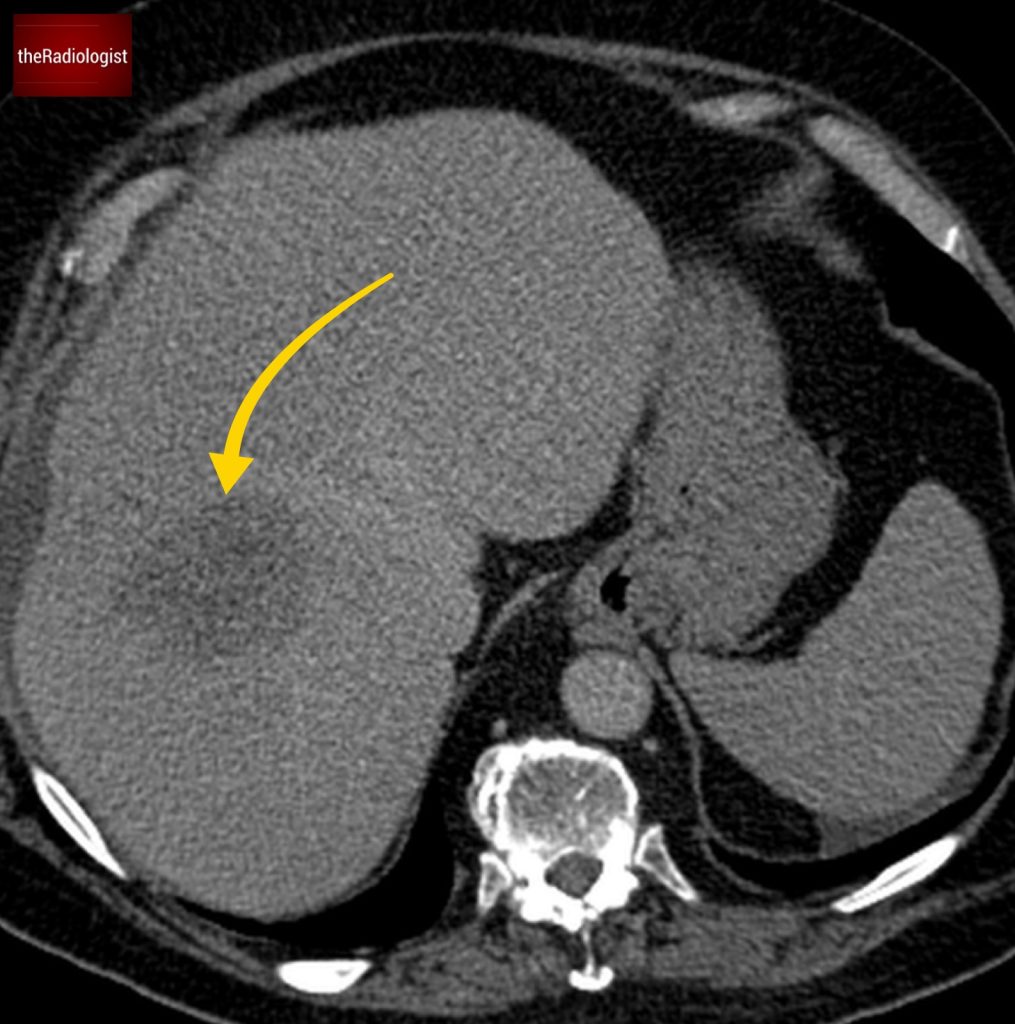

If we look at the psoas muscles on this scan below we can see there is some asymmetry . The right psoas is larger than the left and we’ve lost some of the fat planes within the muscle.

Compare the psoas muscles side by side. The right sided psoas muscle appears expanded with a loss of its normal fat planes.

Also as we scroll down we can see there is fat stranding surrounding the psoas muscle extending into the pelvis.

There is fat stranding surrounding the psoas extending into the pelvis.